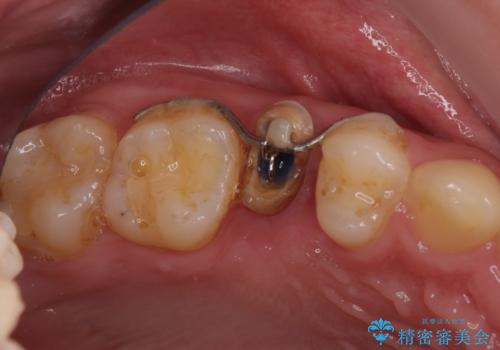

右上の被せものを除去したところ、中で歯が割れていたため、部分矯正で引っ張り出すことになりました。

歯を引っ張り出したり、歯肉の手術の経過待ちの間に、患者様のご希望で他の歯の虫歯治療も行いました。

・両どなりの歯に一時的にワイヤーを接着します。